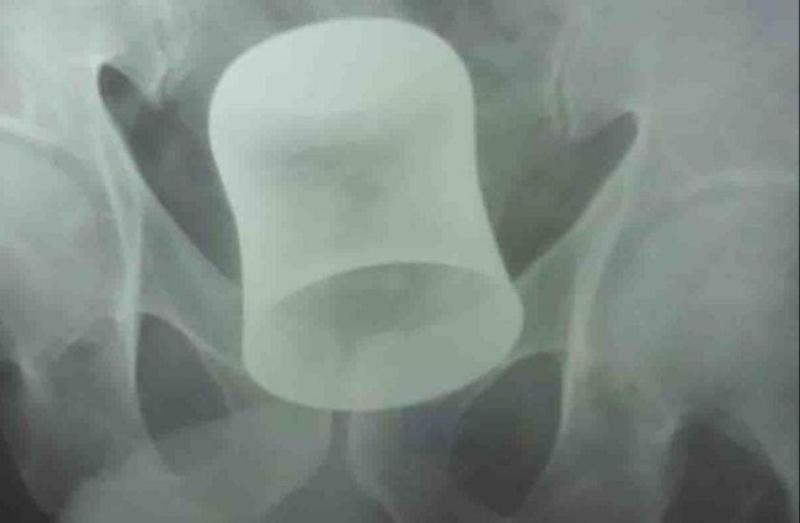

पेट में आंतों के पास फंसा था स्टील का ग्लास

मामला उत्तर प्रदेश के कानपुर का है। बीते 26 जून को एक बुजुर्ग पेट में जबरदस्त दर्द की शिकायत लेकर अस्पताल में डाॅक्टर के पास पहुंचा। जब उसका अल्ट्रासाउंड किया गया तो सभी हैरान हो गए। दरअसल, उसके पेट में स्टील का ग्लास फंसा हुआ था। ये ग्लास आंतों के पास फंसा था। अगले दिन 27 जून को डॉक्टरों ने उसका आॅपरेशन किया। बता दें, पहले गुदा द्वार से ही ग्लासा निकालने की कोशिश की गई, लेकिन एक घंटे तक कोशिश करने के बाद भी वह असफल रहे। इसके बाद पेट में चीरा लगाकर ग्लास को बाहर निकाला जा सका।

डॉक्टर दिनेश के मुताबिक, बुजुर्ग ने बताया कि 10 दिन पहले बदमाशों ने उसे पीटकर बेहोश करने के बाद लूटा। इसके बाद उसके गुदा द्वार में स्टील का गिलास ठूंस दिया, जो उसके पेट में पहुंच गया। इस आॅपरेशन में दो घंटे का समय लगा। रामा हॉस्पिटल एंड रिसर्च सेंटर के सीनियर सर्जन डॉ. दिनेश कुमार ने इसे दुर्लभ आॅपरेशन होने का दावा किया है।

डाॅक्टरों की मानें तो अगर बुजुर्ग के पेट में ग्लास आंतों के पास फंसा था। अगर समय रहते वह अस्पताल न आता या उसका आॅपरेशन नहीं किया जाता तो उसकी जान भी जा सकती थी। बहरहाल, अब उसका आॅपरेशन कर दिया गया है। उसकी हालत स्थिर है आैर वह पहले जैसे रह सकता है।